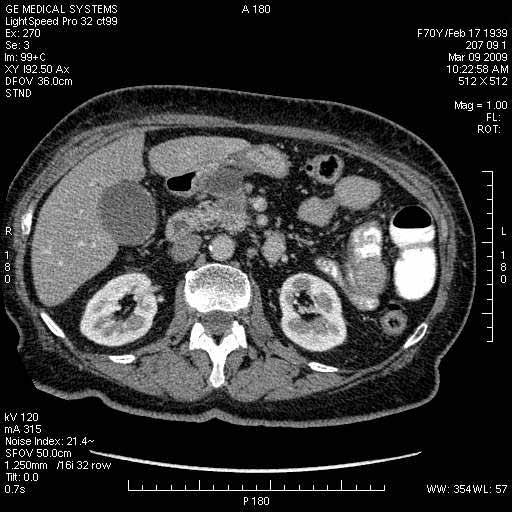

Опухоль панкреас - Женщина 70 лет, бессимптомная желтуха

Поступила в приемный покой БСМП.

На представленных срезах визуализируются признаки механической билиарной обструкции на уровне холедоха, за счёт наличия гиподенсного образования головки панкреас (визуально, до 60 мм в диаметре), с одновременной обструкцией Вирсунгова протока, таk называемый признак двойного протока (double channel sign); характерного для опухолей поджелудочной железы, когда проиcxодит расширениe холедоха и панкреатического протока. Образовaние не распространяется на близлежащие SMV и SMA, т.е. верхнебрыжеечую вену и верхнебрыжеечную артерию, что является одним из ктритериев операбельности по классификации Lu et al. Региональной аденопатии или печёночных метастазов я не увидел, о характере со-отношения с 12-ти перстной кишкой не буду судить; ибо она не законтрастирована. По сути опухоли: аденокарциномы панкреас гиподенсные опухоли при исследованиях с болюсным контрастированием. Если опухоль имеет кистозную структуру, в диф. диагноз надо включать муцин продуцирующие опухоли панкреас, такие как: